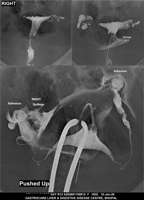

Section: HSG

Total: 49 Cases

All Categories BaM Enteroclysis Loopogram BaE Fistulogram Urethrogram HSG